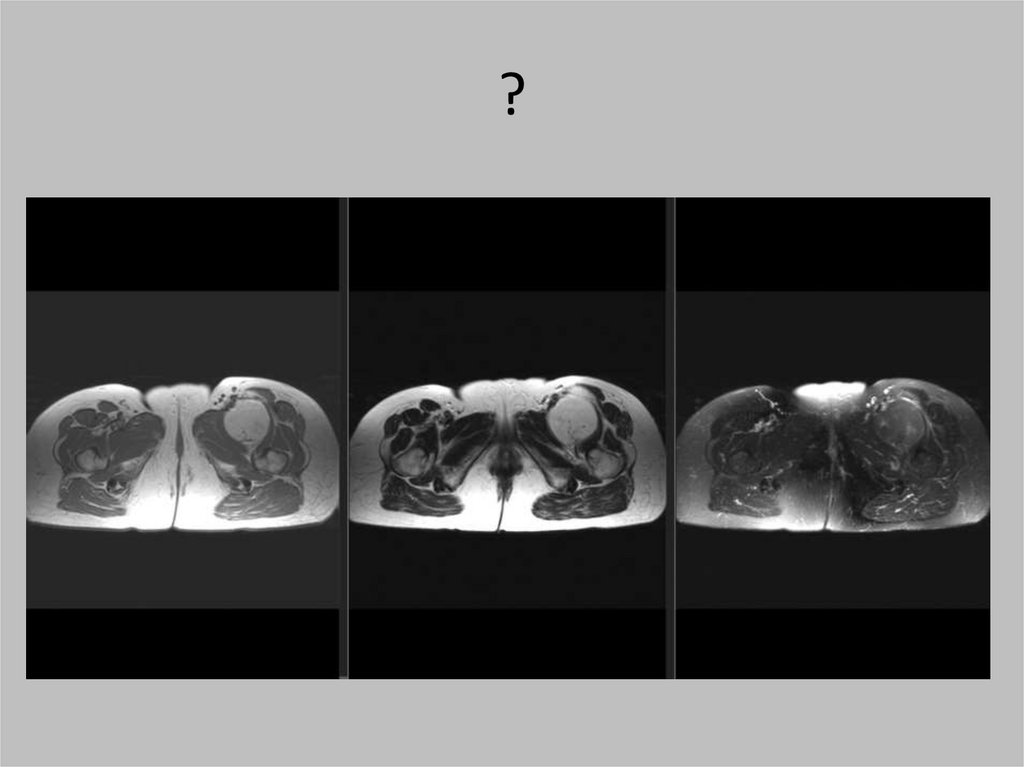

?

100.